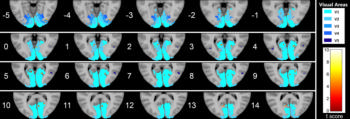

Figure 4. Series of axial section images show T1-weighted imaging–based voxel-based morphometry analysis of occipital cortex. Statistically significant reduction in clusters of gray matter concentration in Parkinson disease group compared with that in control subjects is shown. Only clusters comprising at least five suprathreshold voxels and involving at least one visual area were included in the analysis and are shown in the figure. To help visualization, shaded blue circles were added to highlight all clusters.